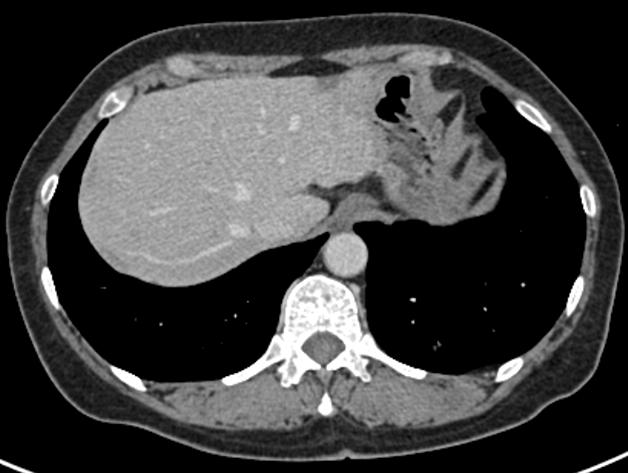

④三线治疗:曲妥珠单抗(汉曲优) 300mg Q3W+吡咯替尼 320mg QD+唑来膦酸4mg Q3M,并予以局部区域放疗。维持治疗至2022.03.31出现新发左肺转移灶及右侧小脑转移灶。行支气管镜检查,并取左肺下叶背段支气管开口见新生物活检,病理提示:(左肺结节)乳腺癌转移,Ki-67(20%,+),ER(-),PR(-),HER2(3+)。右侧小脑异常信号,1.2cm(图5),考虑转移。疗效评价PD,PFS 16个月。

图5. 2022.03左肺及右侧小脑影像图

两个疗程后评估:左肺下叶转移灶较前缩小,1.1cm;右侧小脑转移灶较前缩小,0.8cm(图6)。疗效评价 PR,继续维持该方案。

图6. 2022.05左肺及右侧小脑影像图